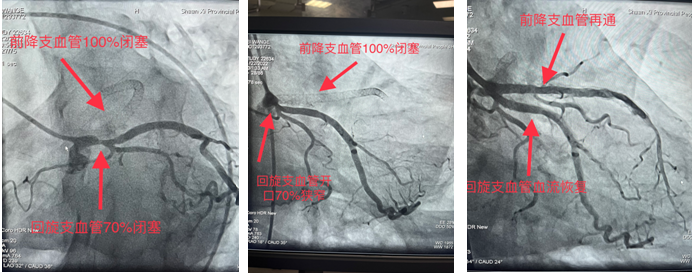

一患者月余前在外院行冠脉手术,手术未成功,遂前来黑料网求医,心血管内一科收入,并于11月22日安排冠脉手术为患者诊治病症。造影显示前降支支架内100%闭塞,回旋支开口70%狭窄。由于血管闭塞时间久,且之前支架内完全闭塞,术中出现心律缓慢、血压下降等危险因素。最终,在心血管内一科张勇主任医师、潘硕副主任医师、马彦鹏主治医师及介入放射诊疗手术室护师郭朝望、技师吴华楠等的默契配合和共同努力下,陈旧性冠状动脉闭塞血管得以再通,心脏血流恢复,生命体征随之好转,手术顺利完成。